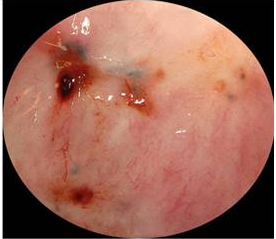

***_EXAME : HISTEROSCOPIA._*** **_PRINCIPAL HISPÓTESE DX : CÂNCER DE ENDOMÉTRIO._** **_FATORES DE PROTEÇÃO PARA CANCER DE ENDOMETRIO : TABAGISMO , PERDA DE PESO , MULTIPARIDADE._** **_PRINCIPAL DIAGNÓSTICO DIFERENCIAL : ATROFIA DO ENDOMÉTRIO._**